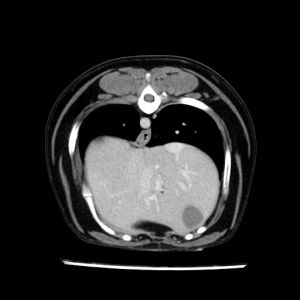

La lesione focale epatica , la ceus,la Tac e il chirurgo .